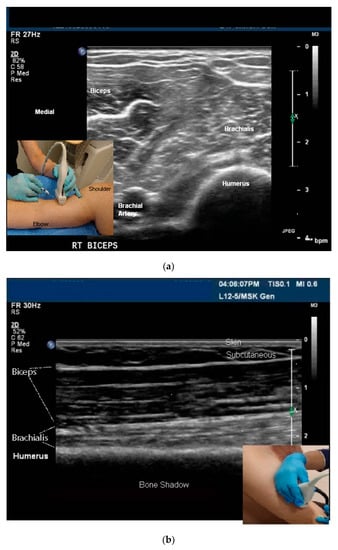

- Skeletal muscle: The sonoacoustic appearance of muscle is a mix of hyperechoic intramuscular connective tissue and hypoechoic contractile fascicles. In long axis or longitudinal view, the contractile elements and connective tissue of skeletal muscles appear as hypoechoic or hyperechoic linear bands or streaks. In transverse view, the muscle has a speckled hypo/hyperechoic appearance from the mix of contractile fascicles and connective tissue viewed in short axis [47,48,49,50]. Figure 1a,b.

- In Plane Technique (IPT). When using an IPT the needle is inserted along the length of the transducer (Figure 6b and Figure 7a). With the IPT, the entire needle and its tip is visualized, an advantage over the OPT. However, this technique can be challenging to perform because the sonographer must keep the needle within the narrow US beam. Another challenge is that optimal needle visualization requires that the needle be inserted and maintained in an orientation perpendicular to the US beam Figure 8a. When inserted at a steep or oblique angle, visualization of the needle may be lost due to needle anisotropy [24,50,54] (Figure 8b).